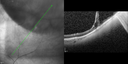

HD Grayscale OCT of Central Serous Retinopathy1043 views